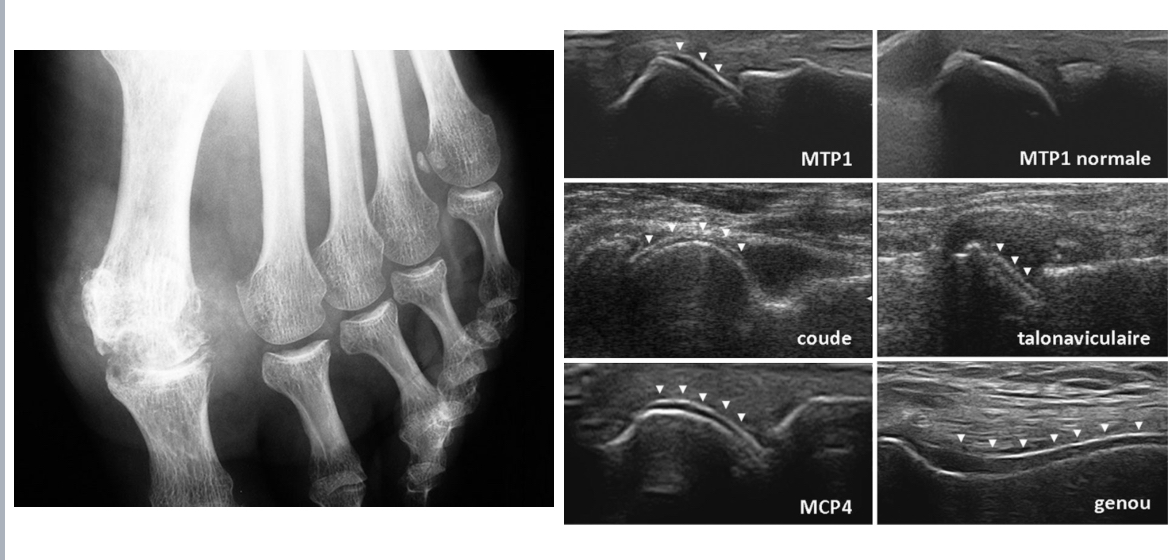

GOUTTE

= maladie de surcharge en urates, chronique, réversible

Radio :

Arthropathie uratique chronique tardivement (géodes ou encoches épiphysaires, conservation prolongée de l’interligne articulaire et ostéophytose marginale)

Écho articulaire :

aspect en « double contour » : dépôt uratique surface cartilage

Tophus goutteux infra-cliniques

POLYARTHRITE RHUMATOÏDE

= réponse immunitaire incontrôlée : production d’auto-anticorps comprenant le facteur rhumatoïde (FR) et les auto-anticorps anti-protéines citrullinées (ACPA), réactions inflammatoire membrane synoviale (synovite)

normale si PR débutante

Mains et poignets : F

Pieds : F+ 3/4

Autres articulations douloureuses : F + P

Thorax:bilan pré-T

Lésions structurales : érosions osseuses, pincement des interlignes articulaires (carpe, MCP, IPP et MTP)

Écho : recherche épanchement liquidien intra-articulaire, synovite, ténosynovite, érosions osseuses infra-radio